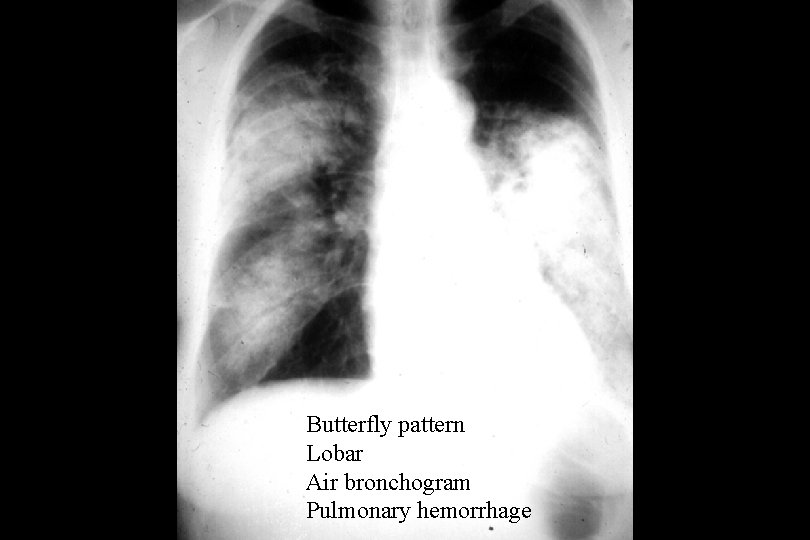

Butterfly pattern Lobar Air bronchogram Pulmonary hemorrhage